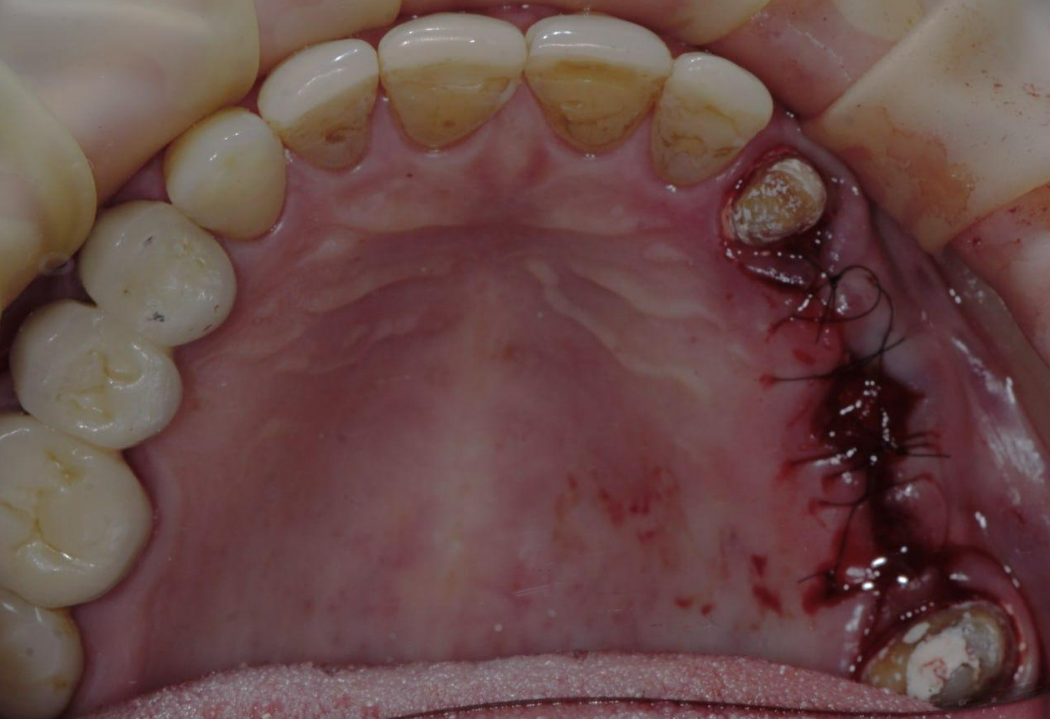

The old PFM bridge was removed, followed by the extraction of the root remnants of tooth 15.

The illustration shows V-Type multi-unit abutments prior to the prosthetic stage: two abutments with a height of 2mm and one abutment with a height of 0.5mm.